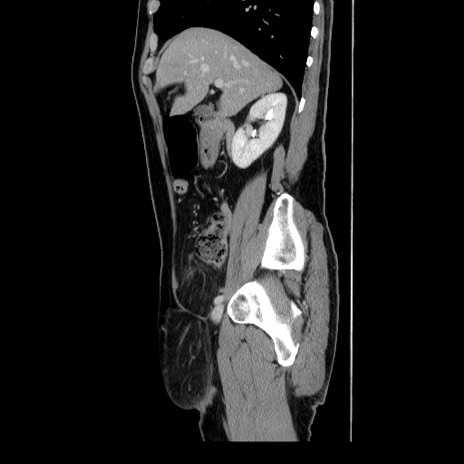

症例34(矢状断像)

【症例】60歳代 男性

【主訴】右鼠径部膨隆

【現病歴】1年程前より右鼠径部膨隆あり。自己にて還納可能だったため放置していた。3時間前より右鼠径部の脱出を認め、還納困難となり受診。

【身体所見】右鼠径部に小児頭大の膨隆あり。弾性硬であり、用手還納は困難。左鼠径部にも膨隆を認める。脱出はなし。